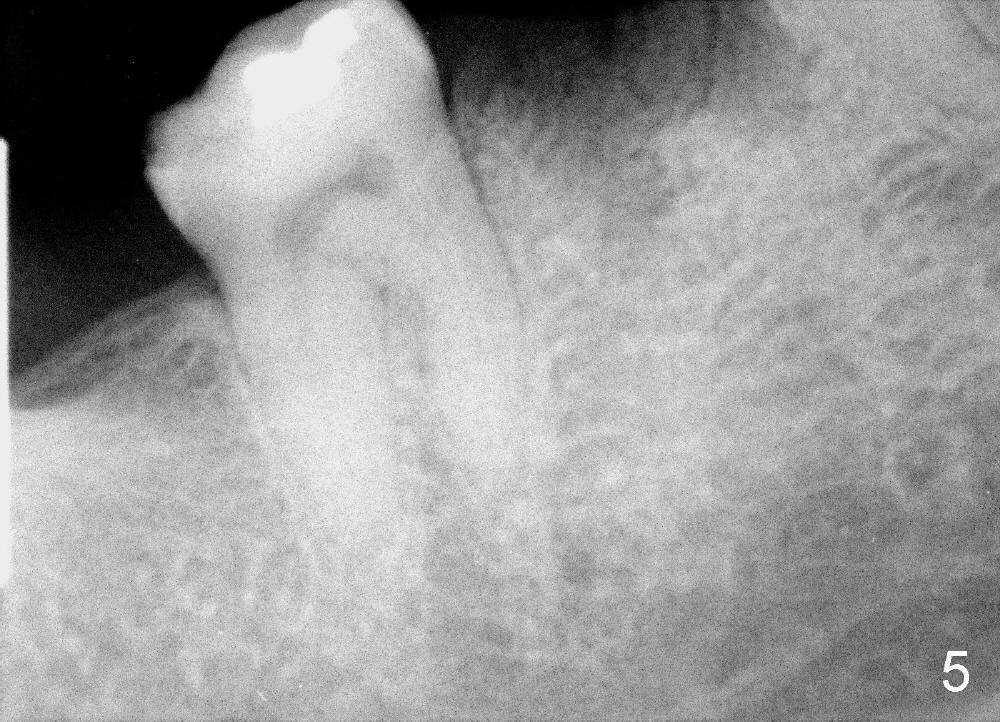

A 38-year-old lady agrees to have implant placement 7 years after loss of the crown of the lower right first molar (Fig.1,2). When the tooth is extracted, the septum is found to be low (Fig.3,4). To confirm it, a PA is taken (Fig.5). To initiate an osteotomy in the septum, it is trans-sectioned with thin osteotomes as shown in Fig.4 insert (black line). A 2 mm pilot drill is placed in the septum (Fig.6: P). The osteotomy is enlarged by 2.5-4.0 mm reamers (Fig.7,8), followed by insertion of 6x17 mm tapered tap at the depth 14 mm (Fig.9). The osteotomy is further enlarged by 4.5 and 5.0 mm reamers. A 6.0x14 mm one piece implant is placed initially. The trajectory is not ideal. A 6.0x14 mm one piece implant is placed initially. The trajectory is not ideal. The implant is removed from the osteotomy partially and reinserted with improved trajectory (Fig.11, compare to Fig.10 (red line)). Primary stability is high. There is not much bone mesiodistally so that the trajectory is easily changed in that direction. After abutment preparation, mixture of autogenous bone (harvested from reamers) and allograft is placed in the residual mesial and distal sockets (Fig.12). To contain the bone graft, an immediate provisional is placed (Fig.13 P). The occlusal plane of the provisional is significantly lower than that of the adjacent teeth to avoid micromovement of the implant. The patient is advised to eat soft food on the left side. Six days postop, the patient returns for prophy. The provisional is removed; the bone graft appears to be incorporating into the socket (Fig.14). After recementation, the provisional remains in place for 3.5 months; PA shows increased bone density in the mesial and distal sockets (Fig.15, compare to Fig.5,11). Due to insurance coverage, the patient defers fabrication of definitive restoration for at least 7 months. The immediate provisional is finally lost 8.5 months postop: the gingiva attaches to the 1-piece implant (Fig.16), while the density of the mesial socket increases (Fig.17 *) with formation of the cortex (lamina dura) coronally (v). Before the provisional (Fig.18 P) is removed for cementation of the definitive restoration, black shadow (*) is noted over the buccal gingiva. It is partially due to buccal placement (Fig.19) and partially due to buccal atrophy over a period of 10.5 months postop. How to prevent buccal placement? Positioning the first pilot drill in the septum buccolingually is a key. Eleven months post crown (Fig.20 C) cementation, the black shadow remains, but there is no tenderness. If the implant threads are immediately underneath the periosteum, there is tenderness.